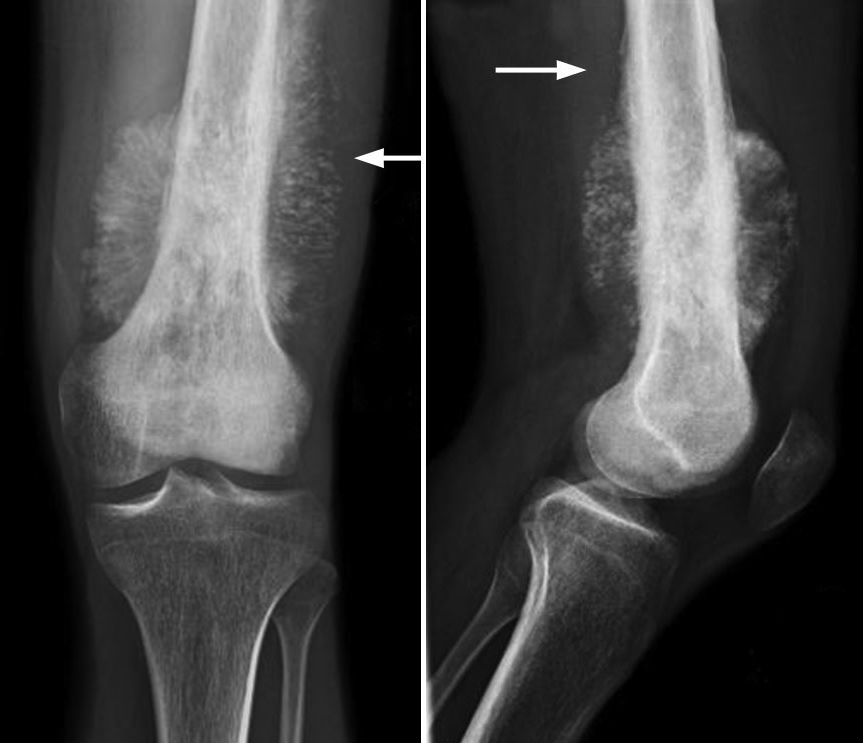

X-ray of osteosarcoma in thighbone

(Left) X-ray shows an osteosarcoma in the femur (thighbone). Note the formation of new bone in a typical "sunburst" pattern. (Right) When viewed from the side, a Codman triangle can also be seen rising from the bone.

Reproduced from Biermann JS, ed: Orthopaedic Knowledge Update: Musculoskeletal Tumors 3. Rosemont, IL, American Academy of Orthopaedic Surgeons, 2014, p. 161.